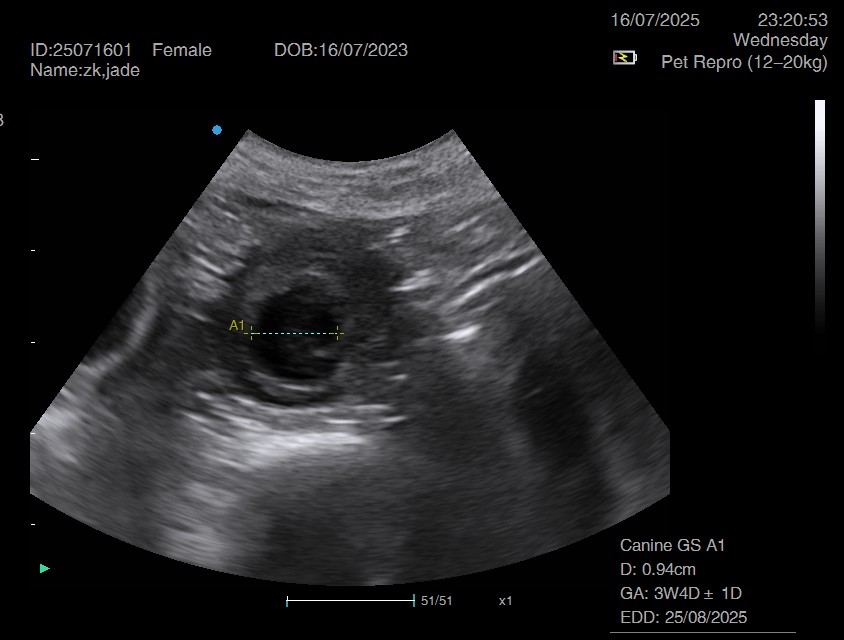

Ultrasound pregnancy scanning is a safe, non-invasive way to confirm pregnancy in dogs and cats, offering breeders and pet owners peace of mind and vital information to support responsible care. It allows us to detect gestational sacs, assess foetal development, and estimate litter size—all while ensuring the wellbeing of the animal.

Pregnancy can sometimes be detected as early as Day 18 post-mating, but scanning at this stage is not routinely recommended. Embryos are still developing and may not be clearly visible, and there is a natural risk of embryo resorption, which can lead to misleading or inconclusive results.

For the most accurate and reliable scan, we advise booking between Day 25 and Day 32, when pregnancy is more easily confirmed and foetal structures are clearer. If an early scan is performed and no pregnancy is detected, we offer a FREE complimentary re-scan after 7 days at the clinic to ensure clarity and support informed decision-making.